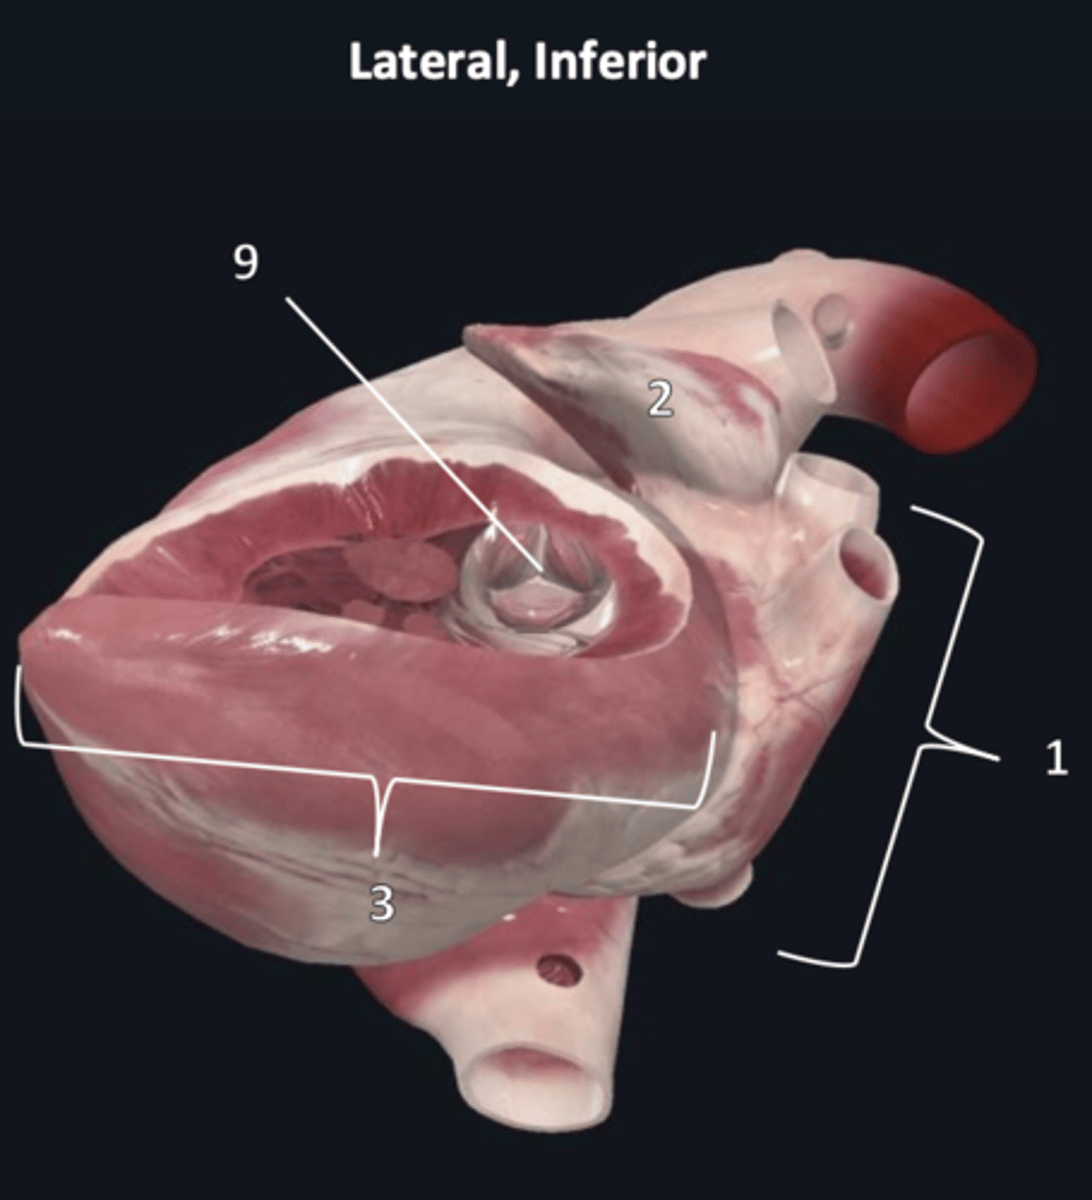

left atrium

1

left auricle

2

left ventricle

3

trabeculae carneae

4

inferior papillary muscle

5

superior papillary muscle

6

chordae tendineae

7

left atrioventricular valve

8 (opening)

aortic semilunar valve

9 (opening)